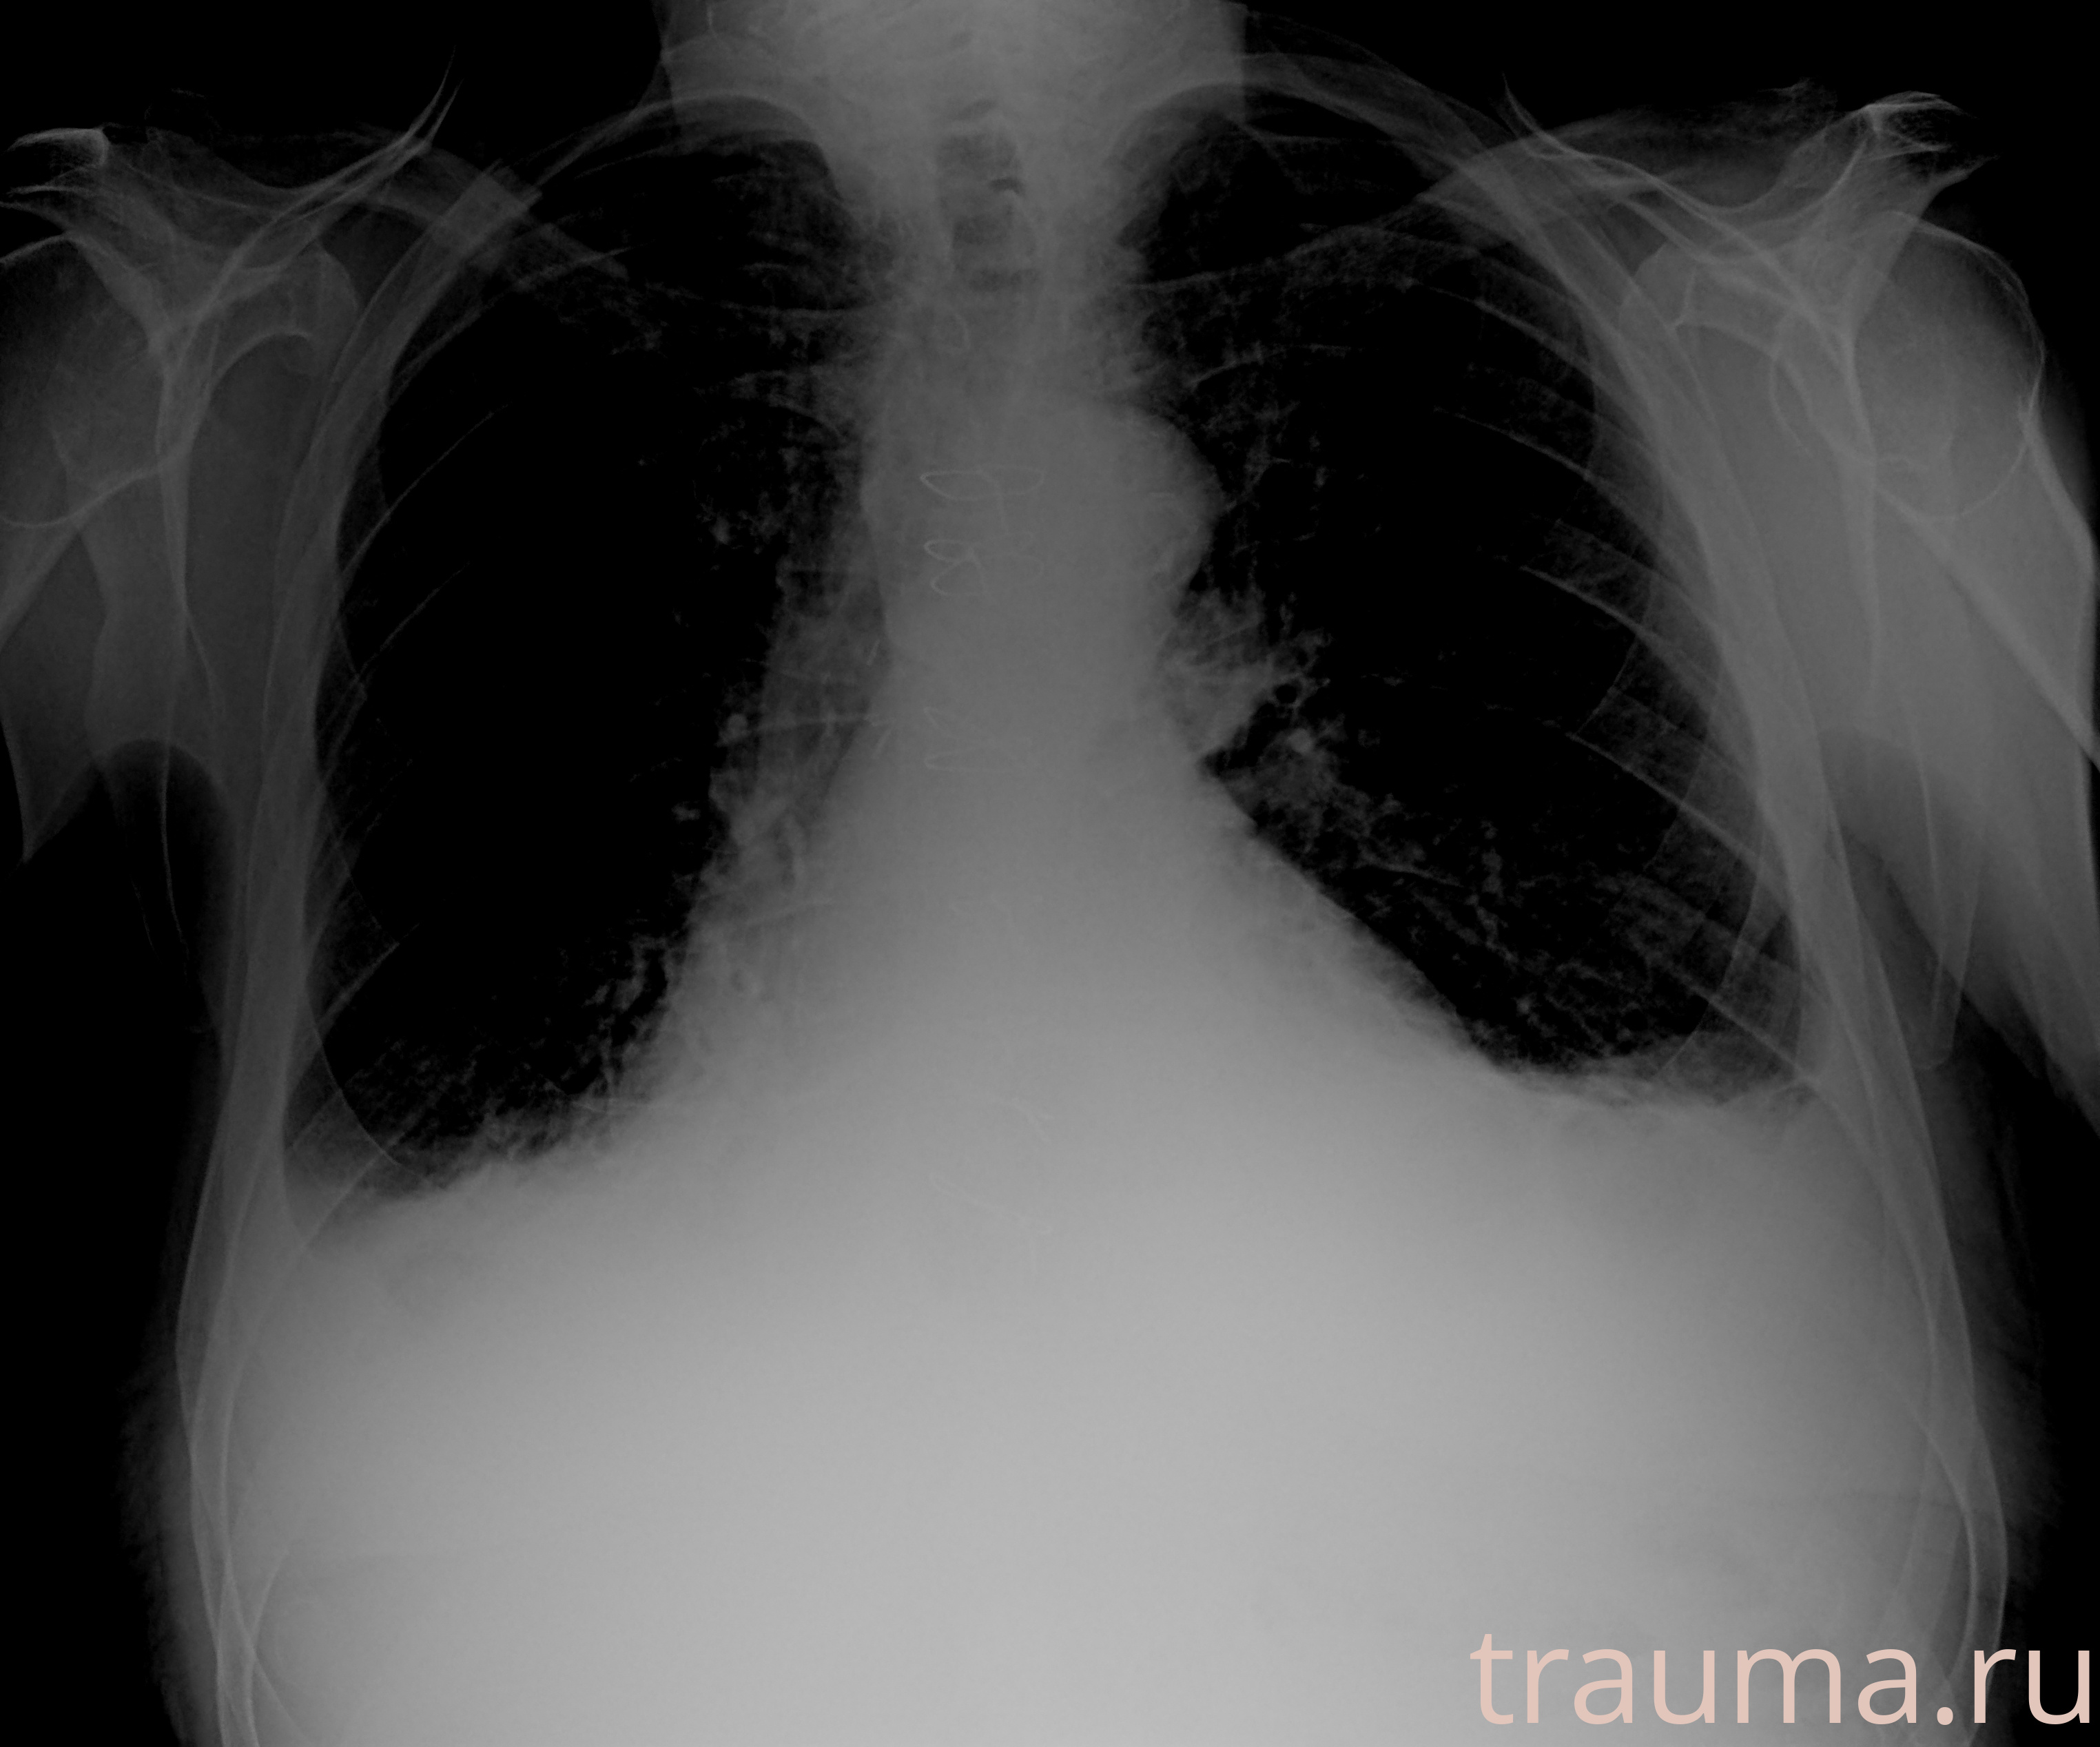

Рентгенограммы

Рентген на дому: по вашему адресу приезжает врач-рентгенолог, травматолог-ортопед с мобильным рентгеновским аппаратом, проводит диагностику травмы или заболевания, делает необходимые рентгенограммы, дает рекомендации по дальнейшему лечению. Получить качественные снимки в домашних условиях возможно благодаря уникальной методике, разработанной МосРентген Центром для института  Склифосовского